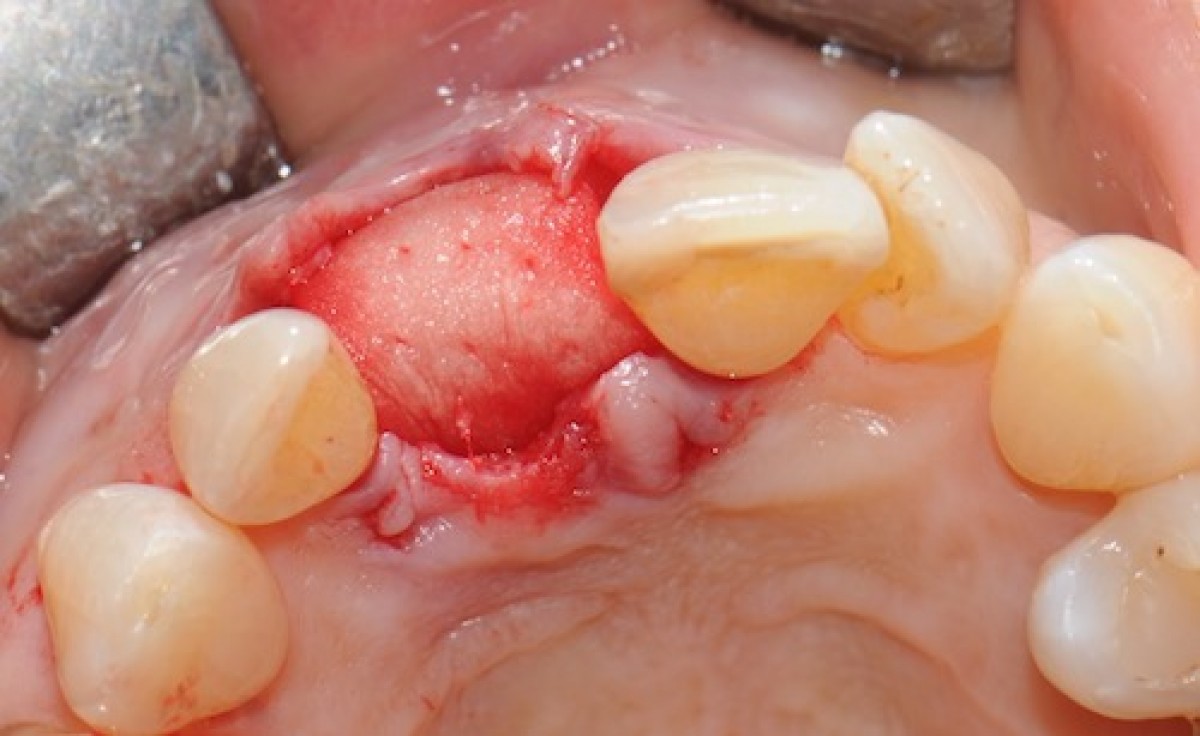

The objective of this prospective cohort study is to test the performance of a new xenogenic collagen matrix as a socket sealing material, to allow second-intention healing of post-extractive sockets filled with a xenogenic bone substitute or with an immediate submerged implant.

10 patients were recruited, presenting a single-rooted tooth scheduled for extraction. After atraumatic tooth removal, the post-extractive alveolus received either a socket preservation procedure or an immediate submerged implant. In both cases, the gingival margins of the alveolus were sealed with a xenogenic collagen matrix (Mucoderm, Botiss Dental, Zossen, Germany). The following parameters were evaluated:

• exposed surface of the matrix at the end of surgery (T0);

• soft tissue healing at 1, 4, 6, and 8 weeks from surgery (T1-4);

• histological aspect of gingiva samples, harvested 20 weeks after surgery (T5);

• aesthetic performance provided by the socket sealing material (T4).

• the mean post-operative exposure area of the matrix was 26.25 mm2 (14.2 to 38.84 mm2 );

• 8 weeks after surgery, full wound closure was achieved in 9 out of 10 sites with healthy keratinized tissue;